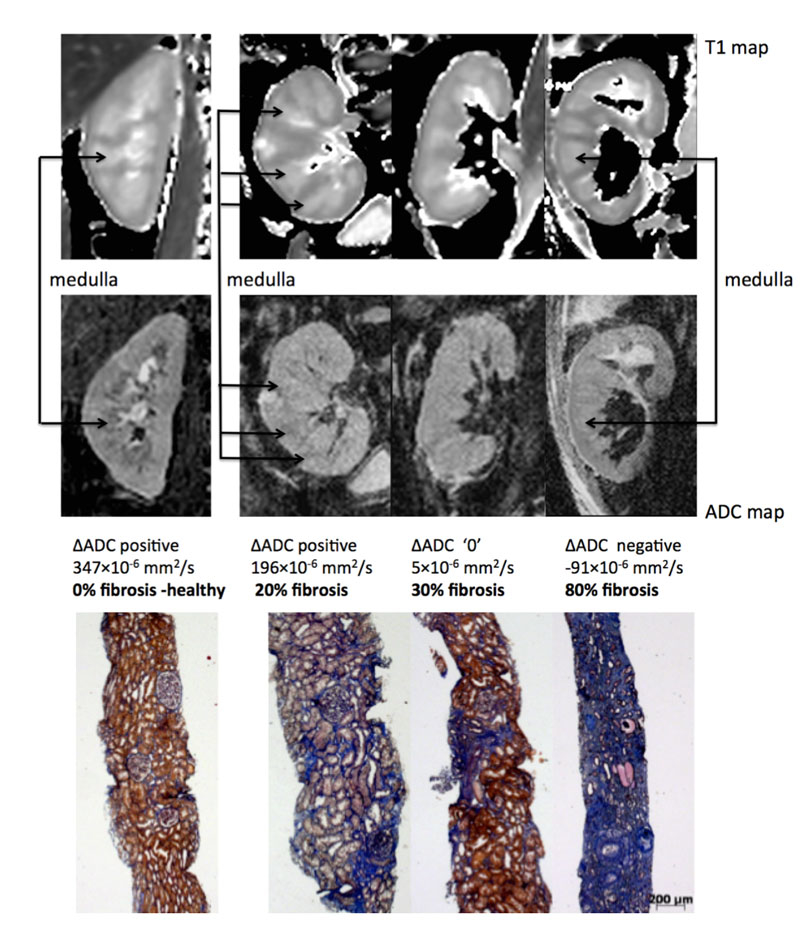

Currently, sequence optimisation is performed to overcome these limitations and decrease diffusion MRI variability. For example, we recently optimised diffusion MRI sequences for the kidney in healthy volunteers. We could demonstrate that a novel sequence (called RESOLVE) largely improved kidney image resolution in healthy volunteers [63]. This enhanced image resolution allowed better differentiation of the cortex from the medulla, and correction of absolute cortical ADC values to medullary values by deriving the difference between cortical and medullary ADC (delta ADC). This correction based on the delta ADC significantly decreased interindividual variability and improved discrimination for cortical fibrosis in patients [64]. Delta ADC correlated well with fibrosis in both experimental models of fibrosis in animals and kidney allograft recipients undergoing biopsies (R2 = 0.64, p <0.001) [64]. Extensive (>40%) fibrosis could be identified by negative delta ADC values (ADC values higher in the medulla than the cortex) (fig. 2). Although more work is needed to validate this index before application in the clinical setting, this study presents encouraging results for diffusion MRI as a novel tool for kidney fibrosis evaluation.

Figure 2 Representative biopsy and magnetic resonance images from patients. Morphological MOLLI T1 map used for the positioning of the regions of interest (top row) and apparent diffusion coefficient (ADC) maps (lower row) for 3 patients showing the different ΔADC cases – positive, zero and negative –with the corresponding fibrosis levels from histology (Masson trichrome staining) [59].